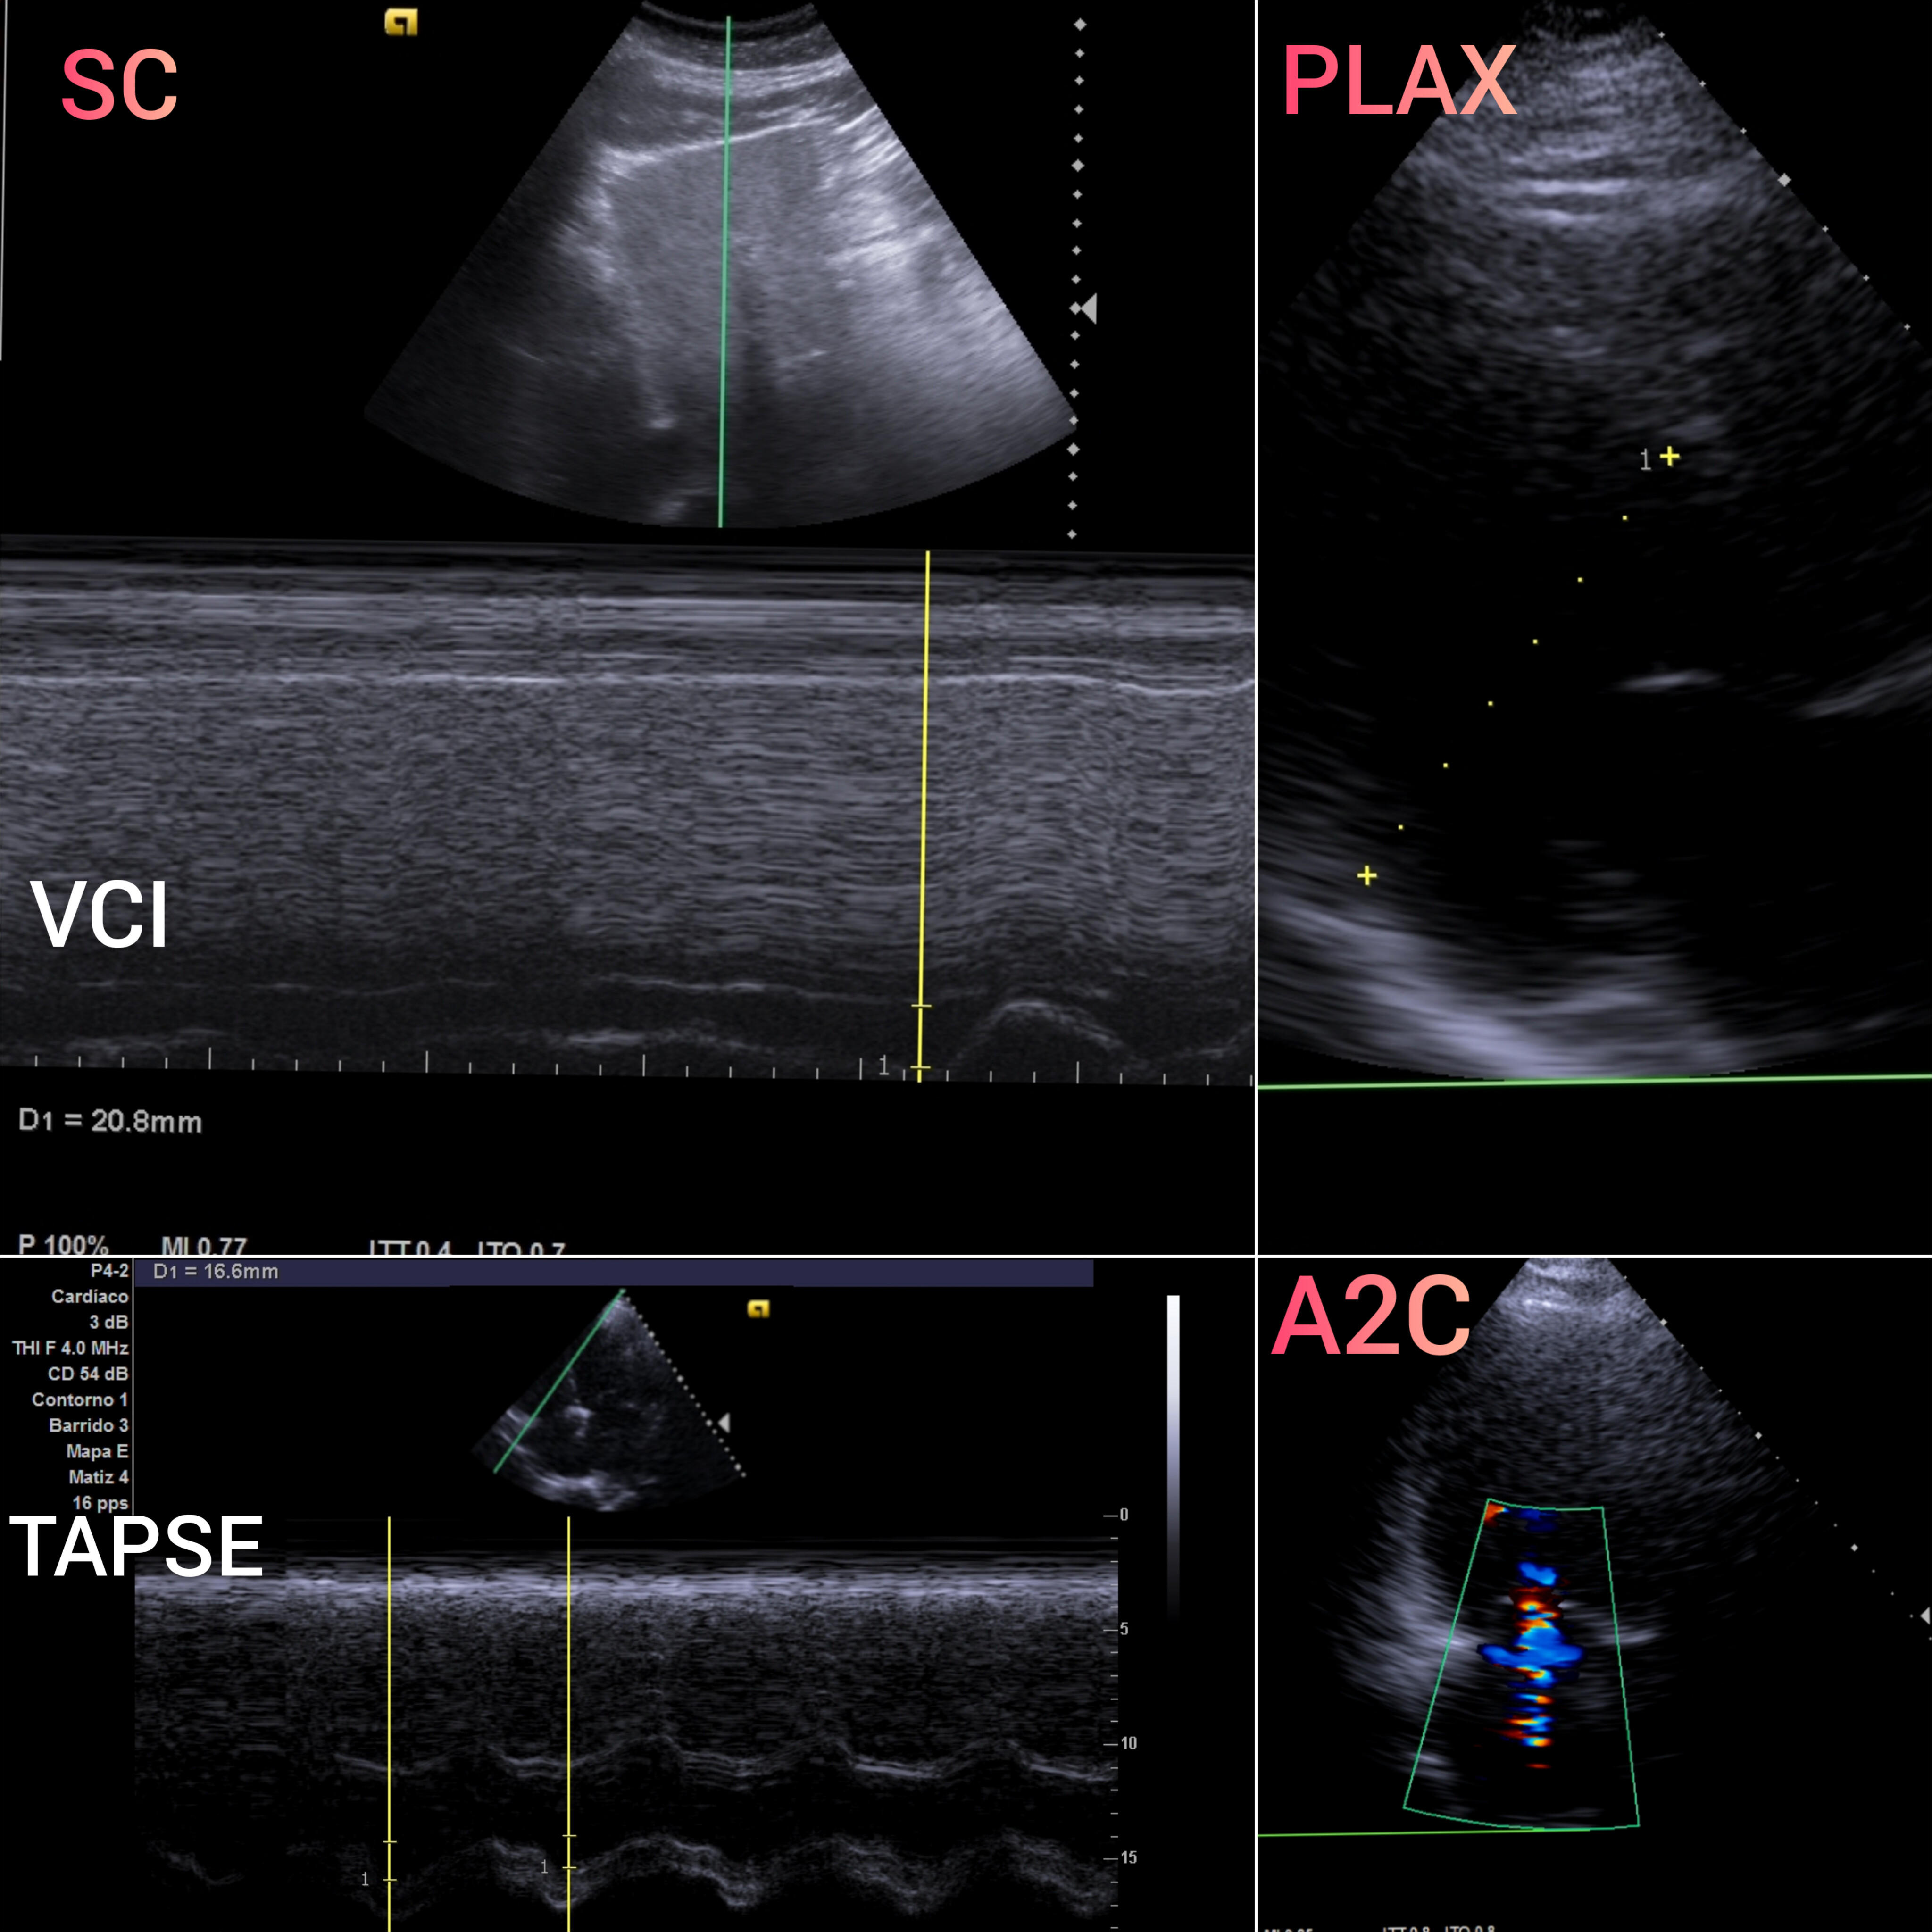

VEXUS: Vena cava inferior VCI 2,1 con colapsabilidad > 50%; Flujo portal y renal continuo.

EcoCardioscopia: Mejoría de contractilidad subjetivamente respecto a previo, cavidades izquierdas dilatatadas tanto VI como AI.

Desde Medicina de Familia, debemos ser proactivos en la detección y control de la IC y sus factores predisponentes. La ecocardioscopia y VEXUS en consulta complementa a ECG, Radiografía y analítica con ProBNP y CEA125. Finalmente, la longitudinalidad en Medicina de Familia nos permite tener presente los antecedentes personales así como los familiares.